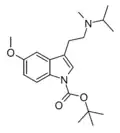

| NB-5-MeO-MiPT | artificial | 1-OCOC(CH3)3, 5-OCH3 | CH3 | CH(CH3)2 | 1-(t-butoxycarbonyl)-5-methoxy-N-methyl-N-isopropyltryptamine | |